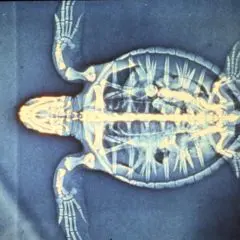

2012- Photo Depictions of Auto-Grafting a Juvenile Green Turtle.